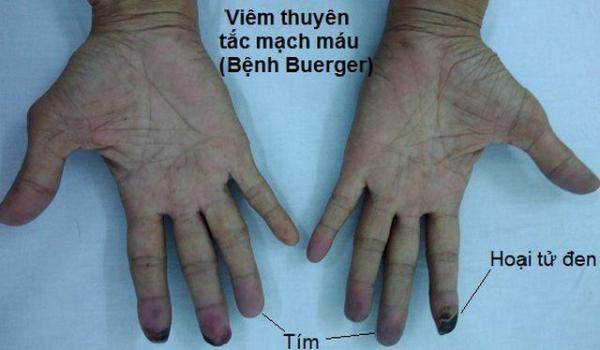

Các bác sĩ của ông đã mô tả sự đổi màu xanh đen trên bàn tay trái, đổi màu sẫm trên bàn tay phải, vết bầm tím và vết thương ở cả hai bàn tay, và nhiều hơn ở hai ngón chân. Các xét nghiệm trong phòng thí nghiệm cho thấy chức năng gan và thận bình thường, các bác sĩ cho rằng cụ ông có mức protein phản ứng C tăng cao, một dấu hiệu viêm khắp cơ thể.

Rõ ràng là người đàn ông này đang bị hoại tử, hoặc chết mô, ở ngón tay và ngón chân. Nhưng có nhiều nguyên nhân có thể của việc này, các bác sĩ của ông đã viết, bao gồm nhiễm trùng, thuyên tắc động mạch và rối loạn đông máu. Bệnh nhân đã được kiểm tra những điều này và các điều kiện khác, tất cả đều âm tính.

Rõ ràng là người đàn ông này đang bị hoại tử, hoặc chết mô, ở ngón tay và ngón chân.

Các bác sĩ cho rằng bệnh nhân bị viêm mạch, tình trạng hệ thống miễn dịch của một người tấn công các mạch máu của mình, gây ra tình trạng viêm dần dần làm dày và làm suy yếu thành động mạch. Điều này có thể dẫn đến việc hạn chế máu đến tứ chi, đem đến vẻ ngoài đáng sợ và tử vong. Bệnh nhân bắt đầu điều trị bằng steroid để giảm viêm, và các bác sĩ đã thực hiện sinh thiết trên các tổn thương để xác nhận sự nghi ngờ của họ.

Bệnh nhân được chẩn đoán mắc bệnh viêm nút quanh động mạch, một dạng viêm mạch ảnh hưởng đến các mạch máu cỡ trung bình. Đối với trường hợp người đàn ông này, các bác sĩ điều trị bằng thuốc ức chế miễn dịch azathioprine và phải cắt bỏ những phần bị đen ở ngón tay. May mắn thay, các bác sĩ mới đây thông báo ngón tay và ngón chân còn lại của bệnh nhân đã phục hồi hoàn toàn.